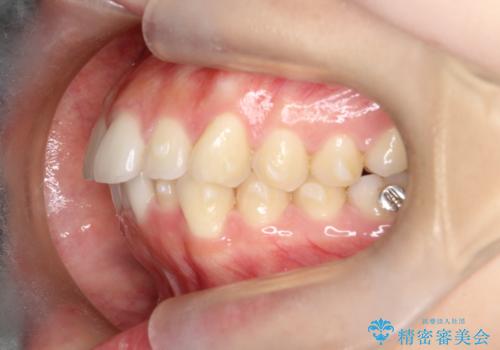

下顎前歯の叢生を短期間で改善

- 患者様は、下顎前歯のガタガタ(叢生)の改善を希望して来院されました。診断の結果、非抜歯で治療可能であると判断し、透明で目立たないインビザラインを使用する矯正治療計画を立案しました。短期間での治療を希望されていたため、IPR(歯間削合)を併用してスペースを確保しながら、効率的に歯を並べることを目指しました。

治療では、インビザラインを用いて計画的に歯を移動させ、短期間での歯列改善を実現しました。IPRを行うことで、抜歯をせずに必要なスペースを確保し、歯列全体を整えました。治療中は、装置の適切な装着時間を守ることが重要であり、患者様にも継続的な協力をお願いしました。また、歯肉や歯根への負担を最小限に抑えるため、歯の移動を慎重に管理しました。結果として、短期間で下顎前歯の叢生を改善し、自然な見た目と機能性を兼ね備えた歯列を実現できました。